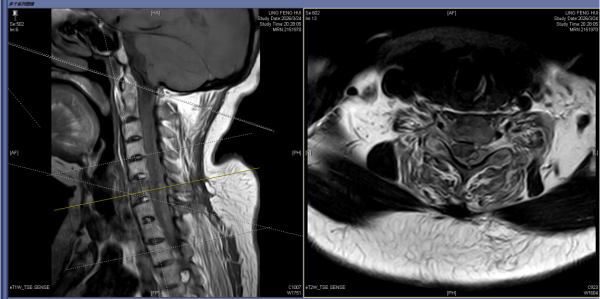

62岁的张阿姨患强直性脊柱炎30余年,3月24日,她不慎摔倒后颈部着地,当即出现四肢麻木、乏力、活动受限等症状,被紧急送往立博体育 急诊科救治,诊断为强直性脊柱炎、C6椎体骨折并C5/6颈椎脱位、颈、胸椎硬膜外血肿,病情危重。

急诊入院核磁共振影像结果

颈脊髓损伤的救治黄金时间为损伤后6—8小时。患者转入脊柱外科二区后,科主任曾浩博士团队立即开启紧急救治通道,经过2天的脱水、激素冲击等对症支持治疗后,张阿姨神经功能有所改善,但危机并未解除。张阿姨长达30余年的强直性脊柱炎导致其颈椎严重僵硬前屈,下颌距胸骨上端仅2-3cm。此次摔倒造成其第5、6节段C6三柱骨折并脱位,颈胸段广泛硬膜外血肿,手术势在必行